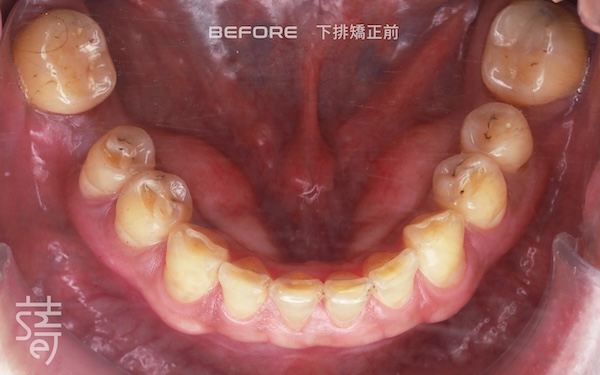

第一階段:隱適美矯正 Stage One: Invisalign Alignment

將牙齒重新排列整齊,調整上下咬合,把原本傾倒的第二大臼齒推回正確位置,為後續植牙和假牙重建打好基礎。

Teeth were realigned, the bite adjusted, and the previously tilted second molars repositioned, laying a solid foundation for implants and prosthetics.